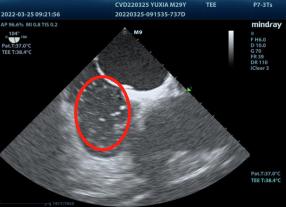

▲超声心动图发泡试验:房水平可见气泡过隔